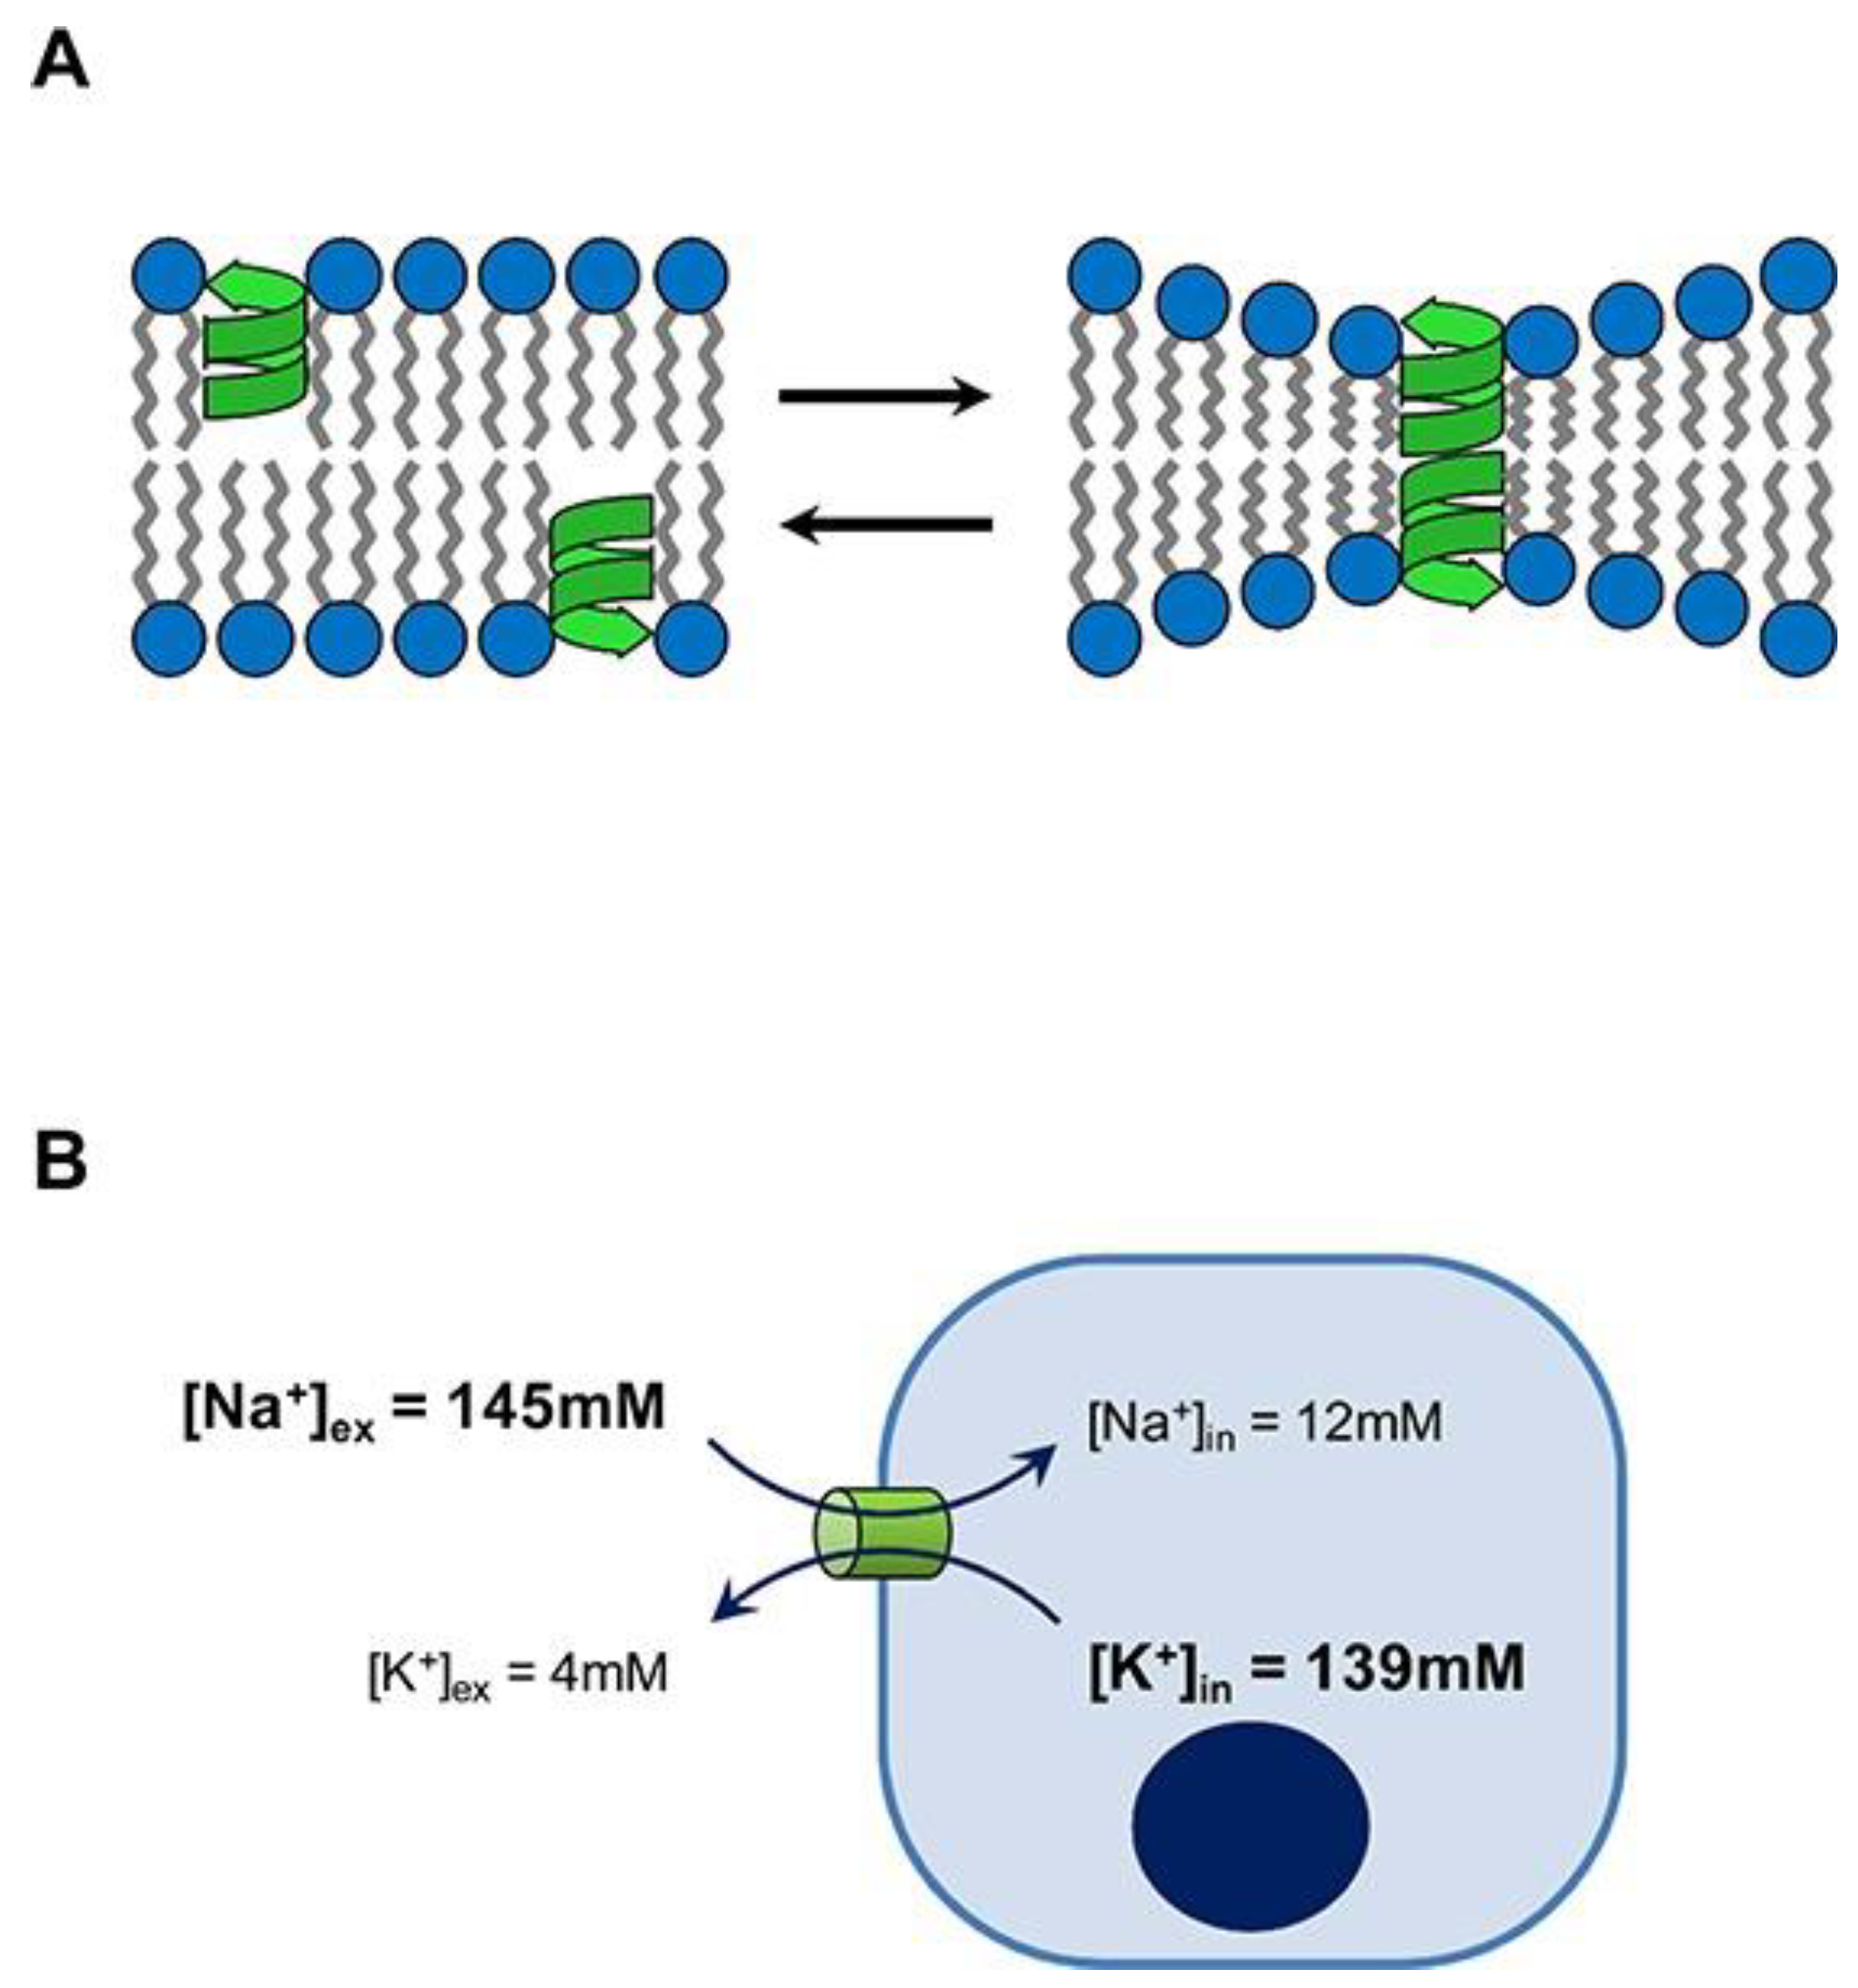

3. Gramicidin D and Its Assemblies